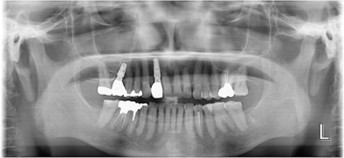

60代 男性

治療前

治療後

治療後- 年齢/性別

- 60代/男性

- 主訴

- 右上7~5/左下6・7

- 治療期間

- 12ヶ月

- 治療費

- インプラント¥1,760,000

骨造成¥220,000

サージカルステント¥110,000 - リスク・副作用

- 術後の腫脹 出血